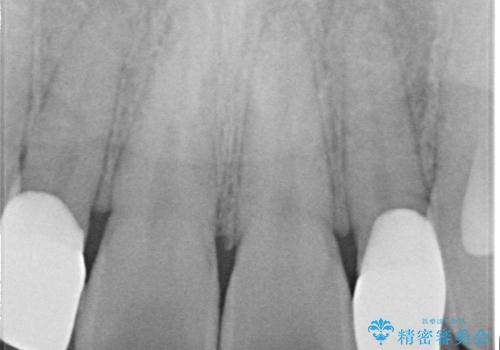

- 当院で矯正治療を行っており、上の前から2番目の歯の形も気になるので治したいと希望がありました。

矮小歯といわれる通常よりも小さい歯であったので、こちらにオールセラミッククラウンを装着して自然な歯の形にすることにしました。

上の前から2番目の歯を少量削らなければならないデメリットはありますが、クラウンの装着により自然な形へすることができました。